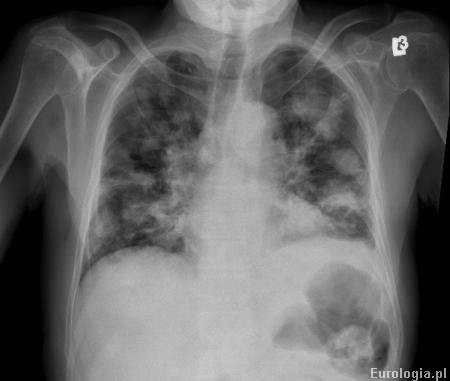

Fot. Zdjęcie RTG klatki piersiowej pacjenta z przerzutami raka jasnokomórkowego do płuc.

Obecność przerzutów u pacjenta z rakiem jasnokomórkowym nerki jest niekorzystnym czynnikiem prognostycznym. Pięcioletnie przeżycie wśród pacjentów z przerzutowym rakiem nerki uzyskuje jedynie 8 - 10% chorych.